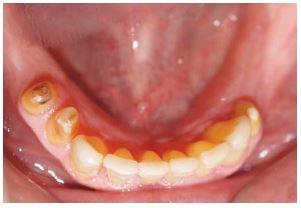

Se realizarón los exámenes clínicos, radiográficos y tomográficos necesarios llegando a los siguientes diagnósticos: Periodontitis crónica localizada moderada en las piezas 12,22,35 y severa en la pieza 15, deformidades y condiciones mucogingivales en rebordes edéntulos: Seibert III: Sextante IV y VI. Lesiones cariosas en piezas: 13,22,24,25, pérdida de sustancia dental causada por: Piezas talladas sin provisionales en piezas 34,35,44,15,12,21,22,24,25. Destrucción coronaria pieza 13, Diagnóstico pulpar: tratamiento de conductos previo piezas 15, 13, 12, 22, 24, Movilidad dental grado 3 en la pieza 15. Asimismo presentó un Desorden Funcional Oclusal teniendo como características: Edéntulo parcial: superior e inferior, Alteración de la guía anterior y disminución de dimensión vertical. (Figura 1 a y b).